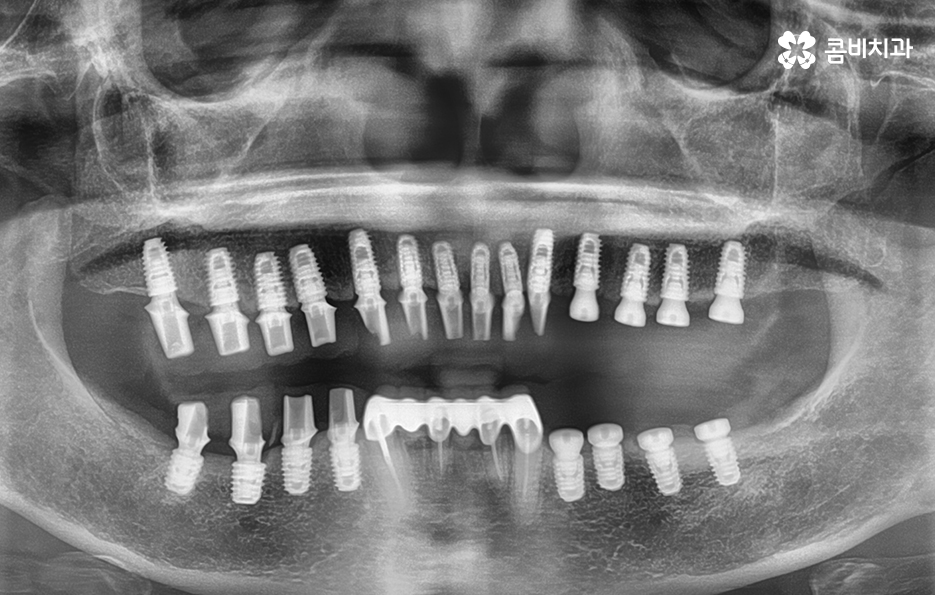

순차적으로 식립이 진행되고 있는 모습

위 사례와 같이 대부분의 치아를 잃게 되신 분들의 경우에는

임플란트가 건강하게 자리를 잡을 수 있도록

시술 과정에 있어서 심혈을 기울여야 합니다.

여러 치아를 잃게 되었을 때 또 한 가지 꼭 유념해야 하는 것은 식립 각도에 따라서 심미적으로

큰 차이가 날 수 있으며 전체적인 교합이

잘 맞물려야 하기 때문에 풍부한 경험과

실력이 필요한 진료에 해당합니다.